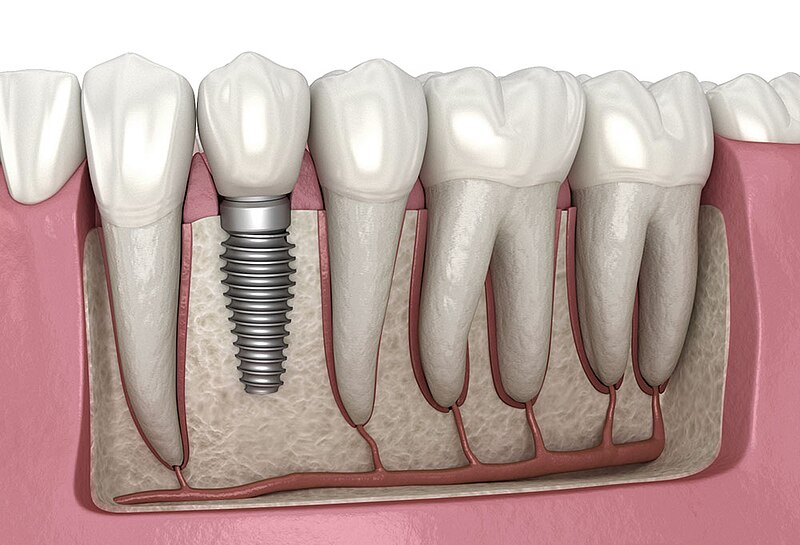

Dental Implants

Permanent and Natural-Looking Tooth Replacement with Dental Implants

G.S. Dental is a premier clinic specializing in dental implants. If you're missing a tooth & looking for a reliable, natural-looking replacement, you've come to the right place! We use the latest technology & techniques to ensure precise dental implant placement and exceptional results tailored to your unique needs. Rediscover your smile and confidence with our expert dental care.

Implant-Supported Dentures

Secure and stable dentures anchored by implants for better functionality.

Zygomatic Implants

Advanced option for patients with severe bone loss, using cheekbone support.